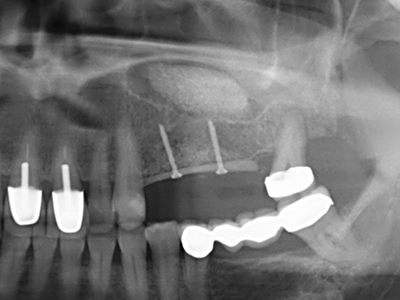

Когато се извършват хирургични процедури върху кост в непосредствена близост до чувствителни структури като кръвоносни съдове или нерви, ротиращите инструменти създават значителен риск за ятрогенно нараняване. Пиезоелектрическите апарати могат да бъдат от помощ при препарация на костно покритие и отстраняване на твърда кост близо до нерви, особено за оголване на нервите след ятрогенно нараняване, както и по време на латерализация на нервите за резекционни и реконструктивни процедури или поставяне на имплант (Фиг. 17-20). Лекият контакт между пиезонакрайника и нерва по принцип не води до нараняване, но ако действате непредпазливо с трионообразни движения или приставки за остатъчен костен субстрат, може да причините временно или перманентно увреждане на нерва. Въпреки това, рискът от увреждане се счита за много по-малък, отколкото при употреба на триони или ротиращи инструменти (Pereira, Gealh et al. 2014).

Както е показано в миналото, всяка костна хирургия представлява възможна индикация за пиезохирургия. По този начин, за препарацията на подвижни сегменти в остеогенеза (Фиг. 23-25) и остеотомия се използват специални накрайници, без да се застрашава снабдяването с кръв в кресталната зона, което е от съществено значение за успеха и на двете техники (Gonzalez-Garcia, Diniz-Freitas et al. 2008).